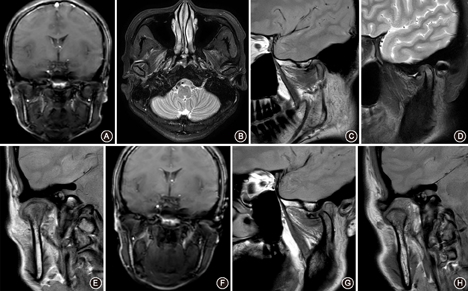

颞下颌关节扫描时先行闭口位检查,再行张口位检查。张口位检查时退出检查床,嘱患者头部保持不动,双手持开口器,调至最大张口舒适位置。扫描序列顺序见表1,所示扫描图像见图3,可以清晰显示关节盘结构及关节腔积液(图4)。

①应提供不同序列、不同位置和不同层面图像;②应标注出左右,先闭口位后开口位或附加定位像;③胶片顺序为闭口位斜矢状位PDWI、斜冠状位PDWI、斜矢状位T2WI、开口位斜矢状位PDWI、斜冠状位PDWI,图片排列可根据医院规定的胶片数量而定。

①以关节盘为中心,放大图像,进行圆形裁剪;②选择关节盘移位最大层面或病变层面;③图像背景应为黑色,对比度清晰,保留序列名称、患者门诊号、姓名、年龄及性别。